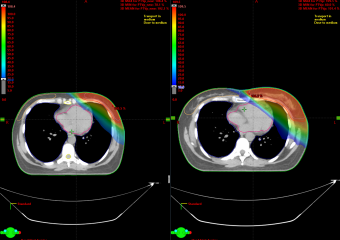

- Точная высокая доза излучения прицельно подается за короткое время. Аппарат дает возможность сформировать излучение, которое при распределении пучков будет точно соответствовать заданному объему – форме опухоли. Это позволяет избирательно облучать злокачественные очаги, щадяще обходя жизненно важные органы (сердце, печень, поджелудочная железа и др.).

- Перед сеансом лечения проводится всестороннее обследование: КТ, МРТ, ПЭТ-КТ, УЗИ и другие процедуры, назначенные лечащим врачом. Затем на аппарате TrueBeam выполняется визуальный контроль: пациент проходит сканирование, в результате которого врач получает данные об актуальном состоянии и положении опухоли, после чего процесс лечения может быть скорректирован и запущен с учетом новых данных. Улучшенный визуальный контроль позволяет точно контролировать процесс облучения без прерывания процедуры.

4. Специальная система позволяет синхронизировать излучение с дыханием пациента, учитывая положение всех органов во время движения грудной клетки. - При проведении SBRT, SRS высокие дозы облучения могут быть доставлены в опухоль, как правило, за 1-5 сеансов в течение одной недели.